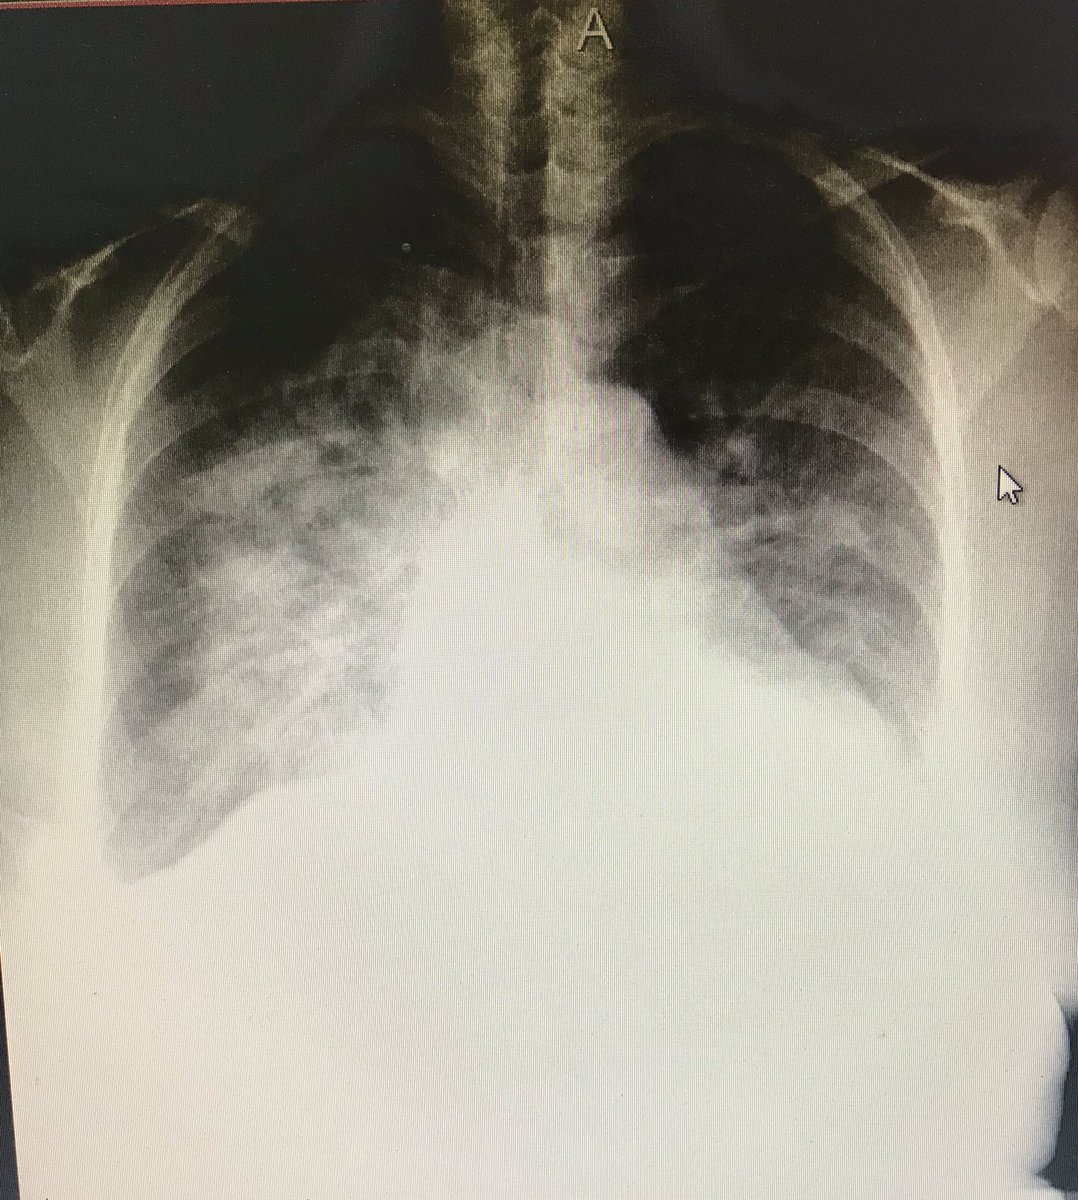

Посмотрев вчерашнее видео у @mal_mars, подумала, почему вышло так, что я сама разочаровалась в отечественной системе здравоохранения. Хоть я ранее не питала иллюзий по этому поводу, в какой-то момент случилась «точка невозврата». И, кажется, я знаю, когда это произошло. Был март 2020го...) Ко мне приехала пациентка с подозрением на пневмонию, предъявляя жалобы на одышку, кровохарканье, слабость, боли в груди. Что немаловажно: за 10 дней до этого она вернулась из-за границы.

Из хронических патологий - ИБС, АГ и СД 2 типа.